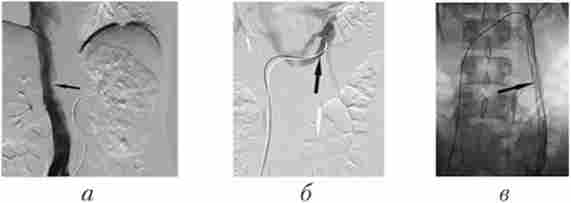

Мал. 29.2. Ангіограми пацієнта з пухлиною правого наднирника, яка проростає праву нирку і праву частку печінки:

а - аортограмме: катетер встановлений в абдомінальному відділі аорти на рівні відходження ниркових артерій (велика стрілка), в проекції правого наднирника і правої частки печінки виявляються множинні ділянки патологічної неоваскуляризації; б - селективна целіакографія: катетер встановлений в черевний стовбур (велика стрілка), в проекції правої частки печінки визначається пухлинна неоваскуляризация (маленькі стрілки); в - катетер встановлений в правій нирковій артерії, яка бере участь в кровопостачанні пухлини (велика стрілка);

в проекції правого наднирника контрастируется пухлинне утворення, що містить велику кількість патологічних судин (маленькі стрілки); г - ангіограми правої діафрагмальної артерії (велика стрілка), також бере участь в кровопостачанні пухлини (маленькі стрілки)